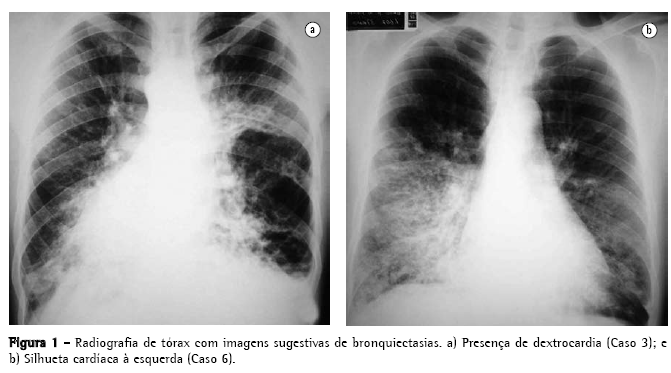

A radiografia simples de tórax de cada paciente mostrou espessamento das paredes brônquicas, atelectasias e imagens radiológicas sugestivas de bronquiectasias, sendo que em cinco casos, também se observou situs inversus (Figura 1).

Os cinco primeiros casos da série tinham dextrocardia, sendo que o Caso 5 apresentava também situs inversus totalis (Figura 3d). O Caso 6 foi o único que apresentou levocardia. Todos os seis pacientes apresentavam roncos e estertores audíveis nas bases pulmonares, eram física e intelectualmente desenvolvidos e ocupacionalmente ativos (Tabela 1).